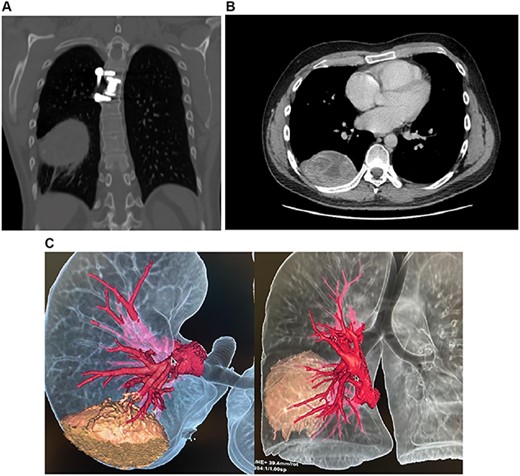

An 8 × 5 × 8 cm low-density heterogeneous mass with a spongiform pattern containing air bubbles and well-defined borders was discovered in the right posterior mediastinum. No lymph nodes or other masses were found (Fig. 1A–C). Gossypiboma, thymomas, lymphomas, germ cell tumors and neurogenic neoplasms were among the differential because of this, cardiothoracic assessment was needed and surgery was decided.

(A) CT, mass is seen in the posterior mediastinum attached to the right lung lobe. (B) CT, spongiform pattern is identified within the mass in the thorax. (C) 3D reconstruction of the CT scan, the mass can be identified in close contact with the lung.